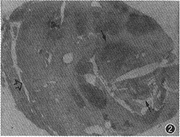

1.肿瘤CT增强影像表现特殊,可分为以下几类:(1)低密度区中伴团状高密度改变24个(图1),病理改变为在比较广泛分布的疏细胞区(Antoni B区)组织中,有相对集中分布的富细胞区(Antoni A区)(图2)。(2)弥漫点状改变20个,点状大小从1~4 mm不等,其密度不等。高密度CT值为60~80 HU,低密度为40~45 HU,两者CT值相差约20 HU。其中呈低密度点状4个;高密度点状4个;高、低密度混杂点状12个(图3)。此20个肿瘤中8个伴有1~2个形态不规则的低密度裂隙样变。高低密度混杂点状分布的病理改变为的Antoni A区、Antoni B区相互交错,分布均匀(图4)。低密度点状改变为比较广泛分布的Antoni A区或胶原基础上出现的零星分布的Antoni B区或微囊集中处,Antomi B区或微囊分布较集中时,即表现为低密度裂隙样改变。较广泛分布的Antoni B区伴少量Antoni A区或胶原则呈高密度点状改变。(3)低密度环伴中央弥漫不同密度点状改变5个,其中单纯为低密度点状或单纯为高密度点状各1个。此低密度环在病理上由Antoni B区组成。(4)中央低密度伴有环形改变8个(图5),环壁厚,环表现各异,其中表现为高、低密度混杂点状分布的3个,单纯低密度点状或高密度点状各2个,环与肌肉呈等密度1个。肿瘤中央的低密度区病理上由Antoni B集中区和(或)陈旧性出血区组成。(5)密度均匀的12个肿瘤中,等密度与低密度各5个,囊性变2个。在病理上等密度多由Antoni A区及胶原组成,Antoni B区较少,分散在Antoni A区及胶原间;而低密度肿瘤(图6)为均匀一致的Antoni B区及部分陈旧性出血组成,几乎无Antoni A区细胞(图7)。囊性肿瘤巨检时见黄色液体流出,囊壁上仍见典型Antoni A、Antoni B区改变。(6)增强特别明显的肿瘤3个,其中2个为弥漫点状改变(图8),1个为厚环。病理显示此3个肿瘤由丰富的Antoni A区组成,夹杂有微囊,而Antoni B区少见(图9),其中仅2个血供比较丰富。

图2 图1肿瘤相应切面组织学表现:黑箭所指的间区为富细胞区(Antoni A区),相当于CT表现的高密度区,中间条形的空白区为切片时碎裂所致;空箭所指为疏细胞区(Antoni B区),相当于CT表现的低密度区